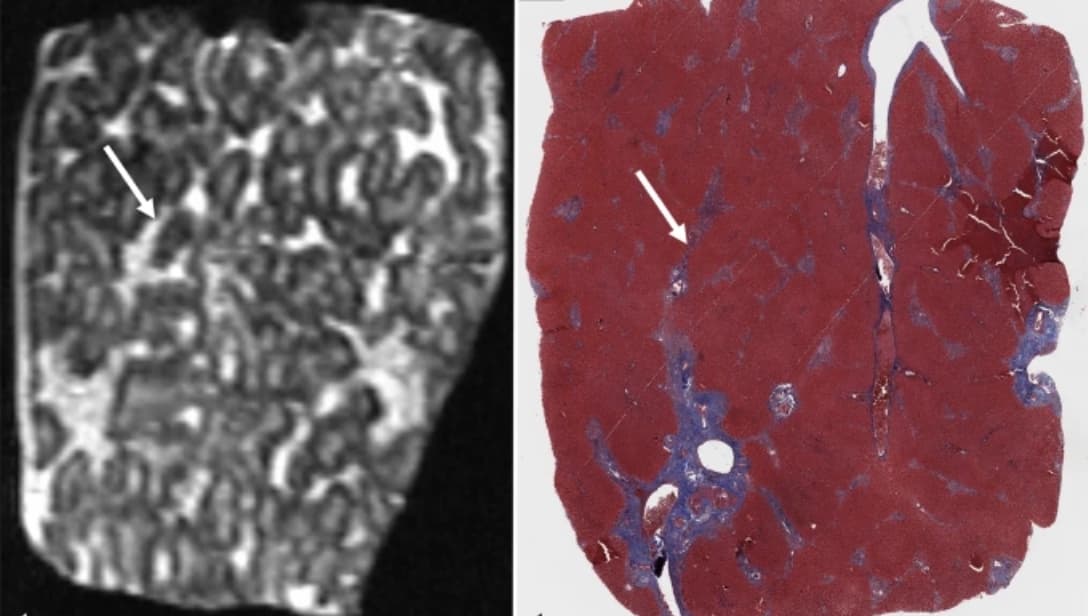

La fraction de densité de proton par IRM est reconnue comme un outil d’évaluation de référence pour quantifier la graisse hépatique. Un travail de recherche publié dans la Revue Radiology évalue la gravité de la stéatose aux moyens de cette pratique. Cet outil IRM est validé par les chercheurs pour...